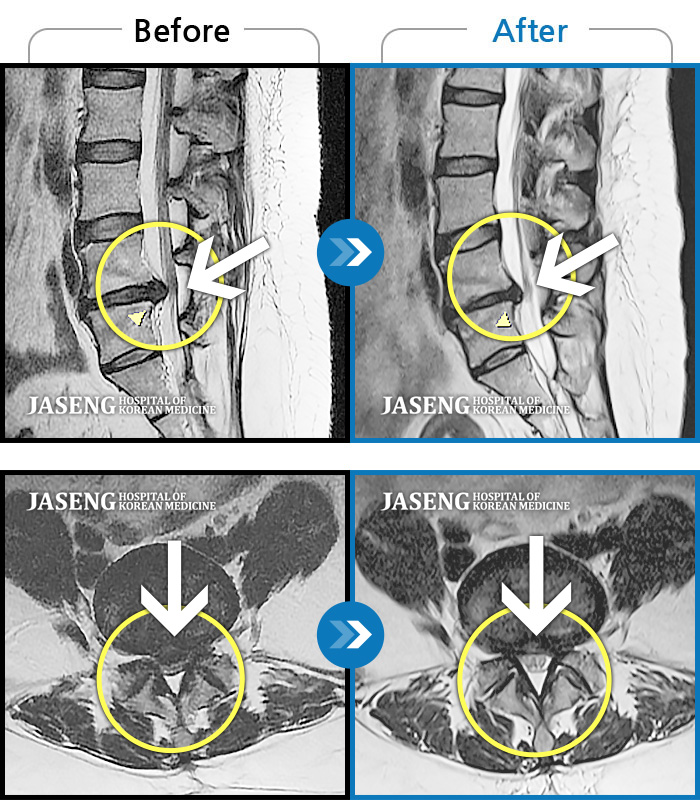

MRI 치료사례

허리 양측 통증, 우측 하지 비증으로 앉을 때 증상 심화